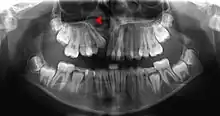

This X-ray film reveals some bone loss on the right side of the mandible. The associated teeth exhibit poor crown-to-root ratios and may be subject to secondary occlusal trauma.

Bone is lost through the process of resorption which involves osteoclasts breaking down the hard tissue of bone. A key indication of resorption is when scalloped erosion occurs. This is also known as Howship's lacuna.[19] The resorption phase lasts as long as the lifespan of the osteoclast which is around 8 to 10 days. After this resorption phase, the osteoclast can continue resorbing surfaces in another cycle or carry out apoptosis. A repair phase follows the resorption phase which lasts over 3 months. In patients with periodontal disease, inflammation lasts longer and during the repair phase, resorption may override any bone formation. This results in a net loss of alveolar bone.[20]